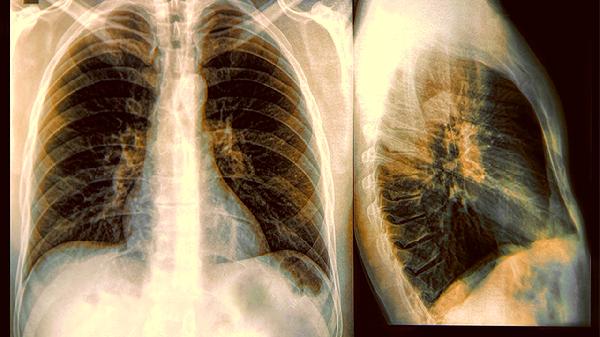

咳嗽只是冰山一角!肺癌真正预警信号是这4种表现

肺癌的预警信号远比我们想象的复杂。很多人以为持续咳嗽就是最危险的表现,实际上身体发出的求.救信号可能藏在更隐蔽的角落。了解这些信号,或许能帮助我们在疾病早期就抓住治疗时机。

1、选择正确检查方式

低剂量螺旋CT是目前公认的有效筛查手段,其检出率是胸片的4-10倍。建议高危人群每年检查一次。